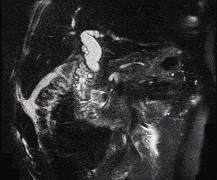

问题 男,78岁,阵发性上腹部疼痛10年伴呕吐,加重1年,影像检查如下图,应诊断为 ( )

选项 A、十二指肠结核 B、肠系膜上动脉压迫综合征 C、十二指肠憩室 D、十二指肠淋巴瘤 E、十二指肠癌

答案 C